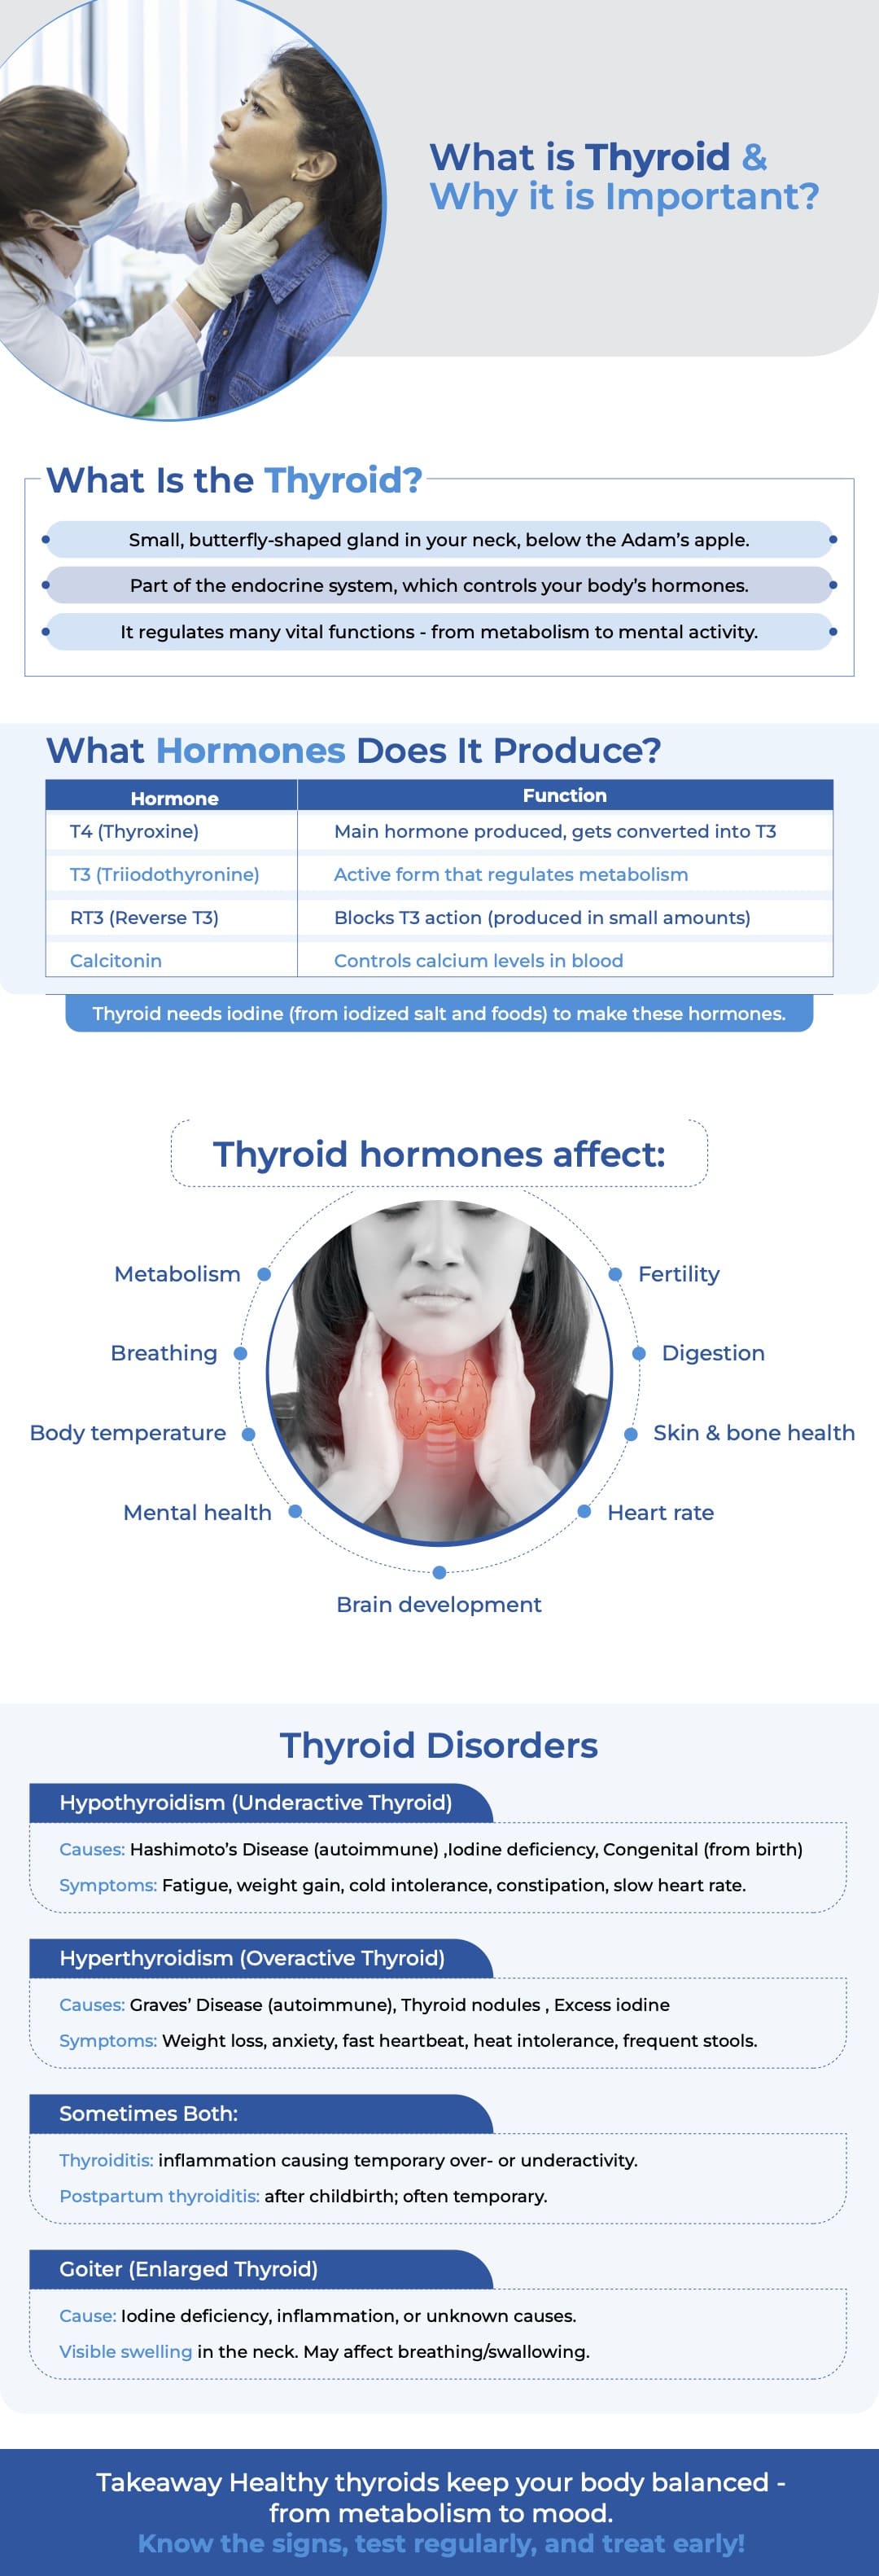

Thyroid Disease

What is Thyroid & Why it is Important?